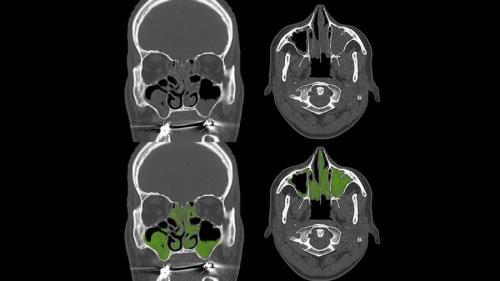

ひとつ目は「内視鏡手術グループ」で、副鼻腔の中に細いカメラを入れて膿や炎症を起こしている部分を掃除し、空気の通り道を広げる手術を受けました。

鼻の内部や副鼻腔が実際にどれだけきれいになったかをカメラで確認したり、鼻の通りや嗅覚がどれくらい回復したのかを客観的に測ったりしました。

具体的には、副鼻腔炎の症状を数字で表す特別なアンケート(SNOT-22スコア)が使われました。

このアンケートでは鼻詰まりや匂いのわかりにくさ、顔の痛みなどの症状がどれくらい強いかを患者さん自身が評価して点数をつけます。

点数が低いほど症状が軽く、高いほど症状が重いことを意味します。

その結果、内視鏡手術を受けたグループの人たちは平均で、6ヶ月後に約18ポイントも症状が改善していました。

一方で抗生物質を飲んだグループの改善は約3ポイントだけで、これは「見た目が同じだが薬の効果はない偽薬を飲んだグループ」の結果とほぼ同じでした。